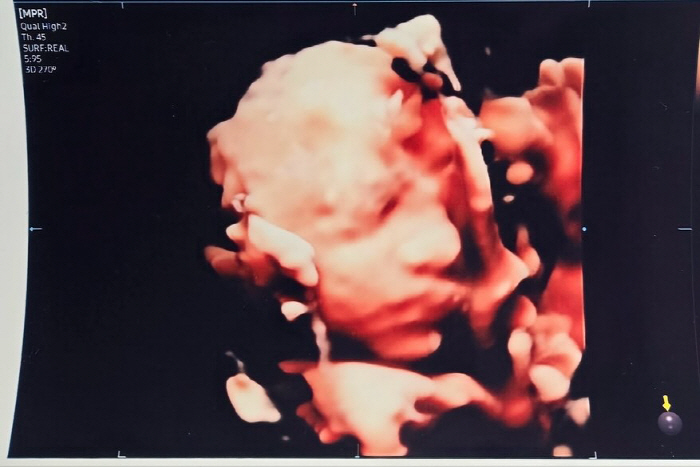

[스포츠조선닷컴 정안지 기자] 배우 손담비가 2세 3D 입체 초음파를 공개했다.

이에 입체 초음파 공개 후 엄마와 아빠 중 누구를 더 닮았을까 관심이 쏠리고 있는 가운데 예비아빠 이규혁은 "담비 한 표 제발!"이라고 댓글을 남겨 웃음을 안겼다.

또한 이를 본 메이비는 "담비야 너 닮았다"고 댓글을 남겼고, 신애는 "코가 오똑하네"라며 박수를 쳤다. 또한 이시언은 "형님 닮으심"이라고 했고, 이현이는 "어머!! 너 얼굴 있어!"며 웃었다.